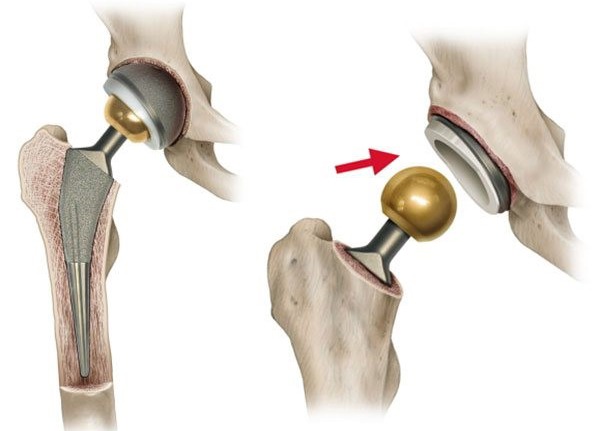

Эндопротезирование тазобедренного сустава: фото и схемы

Раздел: Необычные решения